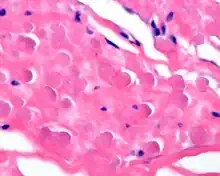

In general, the tumor is an ill-defined, nonencapsulated, rubbery, and firm, white lesion with interspersed fat. The tumors can be quite large (up to 20 cm), although most are around 5 cm.[4]

By microscopie view, there is an admixture of heavy dense bands of collagenous tissue dissected by fat and abnormal elastic fibers. The elastic fibers are often quite large and are easily identified. The elastic fibers are coarse, thick, and darkly eosinophilic, often fragmented into globules, creating a "string of pearls" or "pipe cleaner" appearance. Because of degeneration, the elastic fibers will appear as globules with a serrated or "prickled" edge.[4]